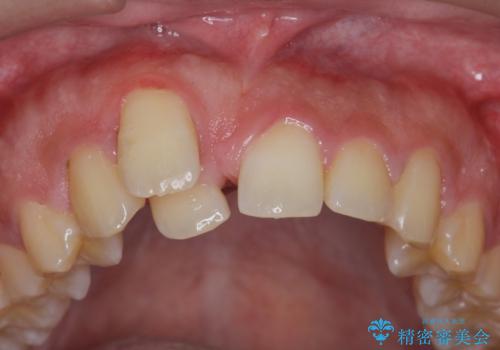

正中過剰埋伏歯で生じた前歯の審美障害 矯正治療での改善

- 前歯の見た目に悩まれて来院されました。

当初他院では、抜歯を行いセラミックブリッジを提案されていましたが、他の方法はないかと総合歯科治療を行う当院へと相談来院されました。

「時間がかかっても良いので、できれば歯を抜かずに矯正治療で治したい。」という強い希望があったので、矯正治療で歯並び・審美性の改善を計画します。